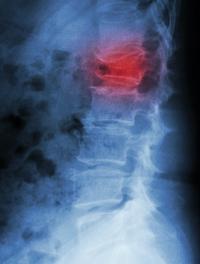

La spondylarthrite ankylosante (SPA) est un rhumatisme inflammatoire chronique qui se caractérise d’abord par l’atteinte du squelette [...]